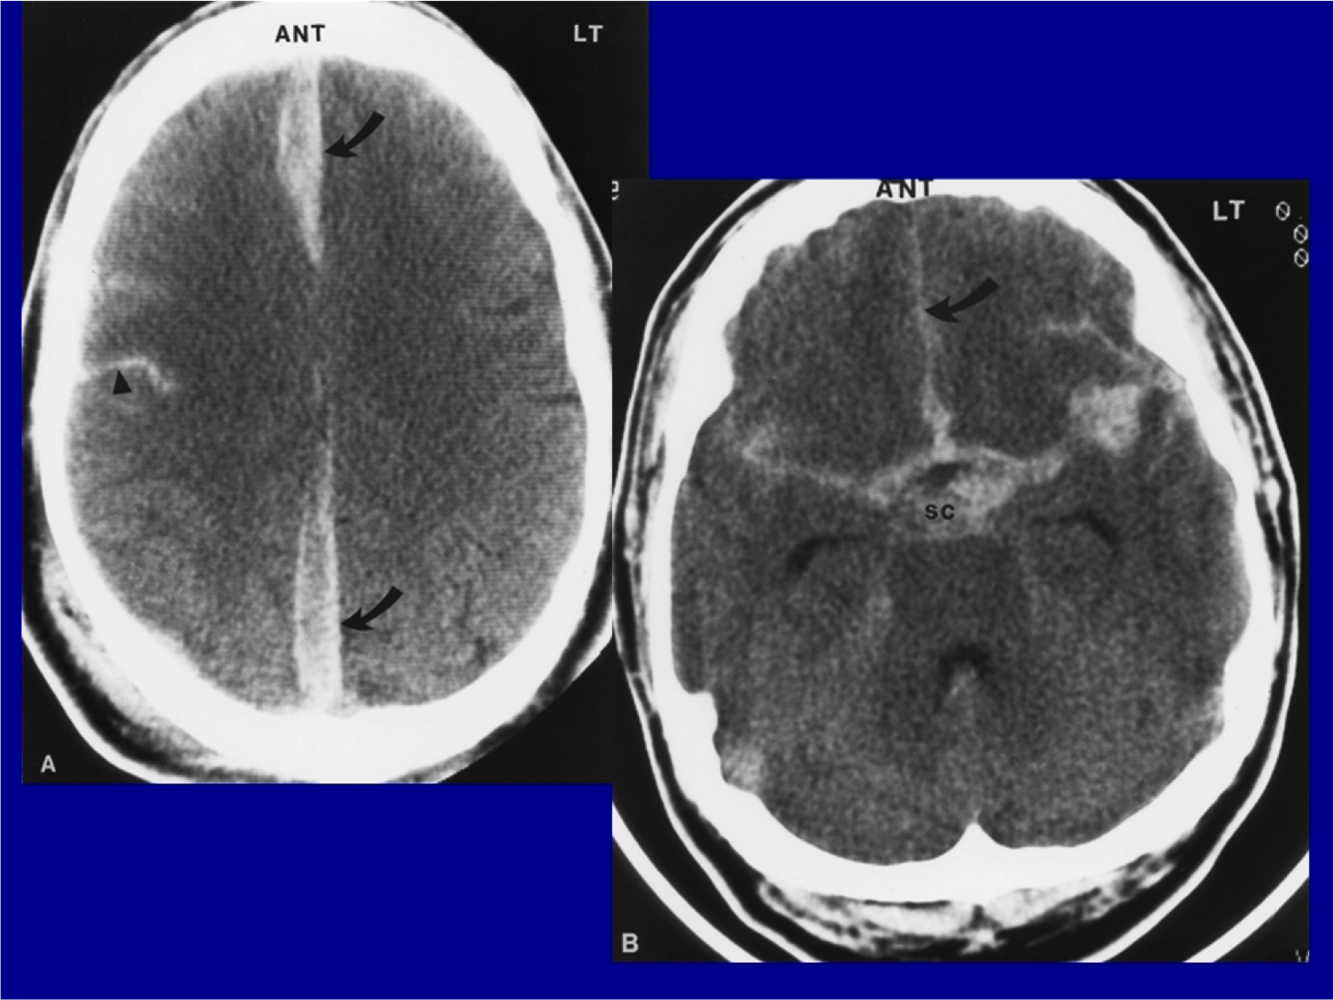

What is shown?

Subdural hematoma

subarachnoidhemorrhage.